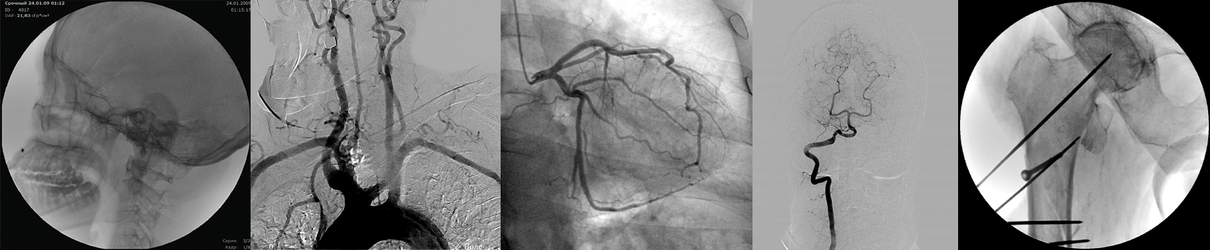

Рентгеновский аппарат типа С-дуга – современное диагностическое оборудование, предназначенное для проведения рентгеноскопических и рентгенографических исследований, а также для осуществления интервенционных процедур под лучевым контролем. Название устройства связано с характерной формой штатива в виде буквы «C», на одном конце которого расположена система, воспринимающая рентгеновское излучение, а на другом – трубка-излучатель.

Такие установки используются практически во всех отраслях современной медицины: в травматологии, ортопедии, урологии, абдоминальной хирургии, интервенционных процедурах, ретроградной холангиопанкреатографии. Открытая конструкция и специфическая форма делают С-дугу незаменимым инструментом в операционной и в диагностических отделениях благодаря созданию беспрепятственного доступа к телу пациента.